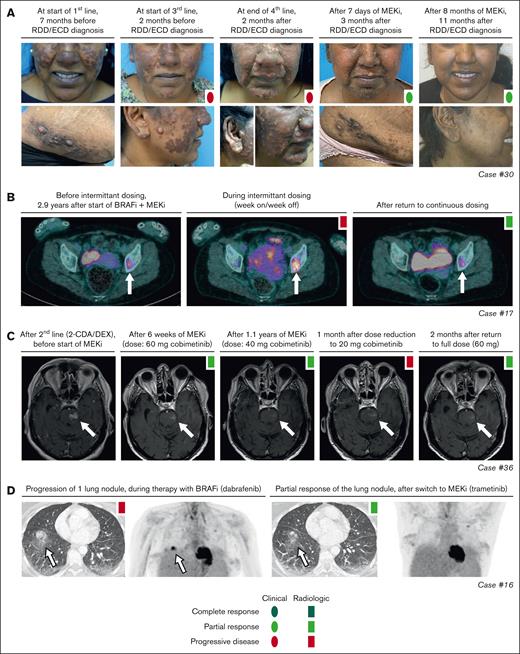

Response and rare disease progression on targeted therapy. (A) Photographs showing response of skin lesions in case 30 with RDD/ECD to conventional therapies and targeted treatment with cobimetinib. (B) Axial PET-computed tomography (CT) images of case 17 with ECD showing increased fluorodeoxyglucose (FDG) uptake of a left acetabular lesion (indicated by a white arrow) during intermittent dosing of dabrafenib/trametinib. After returning to continuous therapy, PET-CT showed decreased FDG uptake in the acetabular lesion, consistent with a recaptured PR. (C) Axial T1-weighted gadolinium-enhanced MRI images of case 36 with CNS-RDD showing an initial PR of contrast-enhanced brain lesions to treatment with cobimetinib, and subsequent progression of brain stem lesions after dose reduction to 20 mg/d. After return to full dose (60 mg/d), lesions decreased again, indicating a recaptured response. (D) Axial CT and PET images of case 16 with ECD showing progression of an FDG-avid lung nodule during treatment with dabrafenib, and partial resolution of this nodule after switch to treatment with trametinib. 2-CDA, cladribine; DEX, dexamethasone; BRAFi, BRAF inhibitor; MEKi, MEK inhibitor.

Objective responses were observed in 25 of 27 (93%) patients (Figure 2), whereas the remaining 2 patients either had SD (patient 26) or stopped treatment before response evaluation was possible (patient 18). Six patients obtained a CR, including 3 with LCH and individual patients with ECD, CNS-XG, or HS. Notably, the patient with HS (patient 37) stopped trametinib after 3.5 months, received an allogeneic hematopoietic stem cell transplantation, and was in complete remission at last follow-up (Figure 2). Objective responses were substantiated by imaging in 22 of 25 cases, and exclusively based on clinical and/or laboratory evaluations in the remaining 3 cases. For example, CR in case 2 (a 1-year-old girl with high-risk multisystem LCH) was based on marked clinical improvement and normalization of hemoglobin, platelet, and albumin levels. In case 30 with RDD/ECD, the objective response was also evident from rapid clinical improvement of skin lesions within days after start of cobimetinib (Figure 3A), with response of internal lesions captured by imaging after 8 weeks of treatment. Finally, the radiographic response in case 16 with ECD involving the lungs corresponded to a marked improvement of pulmonary function (transfer factor for carbon monoxide from 22% to 45%) and self-reported quality of life.

Objective responses were generally durable, although there were instances of PD in 11 of 27 (41%) patients (Figure 2). In 10 of 11 patients, these instances were related to a dose reduction or therapy interruption. Responses were recaptured in 9 of 10 cases after the dose was increased or therapy was restarted. For example, case 17 with ECD had increased fluorodeoxyglucose uptake in a left acetabular lesion after intermittent dosing of dabrafenib/trametinib (week on/week off; initiated as exit strategy after 3 years of treatment). After returning to continuous therapy, fluorodeoxyglucose uptake in the acetabular lesion decreased again (Figure 3B). Similarly, in case 36 with CNS-RDD (Figure 3C) and cases 27 and 28 with CNS-XG (Figure 4), disease progression was observed on MRI after dose reduction or stop of targeted therapy. In all 3 cases, objective responses were recaptured after dose escalation or restart of therapy (Figure 2). Potential acquired resistance to targeted therapy was only observed in case 16 with ECD, who had progression of a single lung nodule despite adequate intake and dosing of dabrafenib (150 mg twice daily). No biopsy of the nodule was taken. The patient subsequently switched to trametinib, which resulted in a PR at the end of follow-up (Figure 3D).